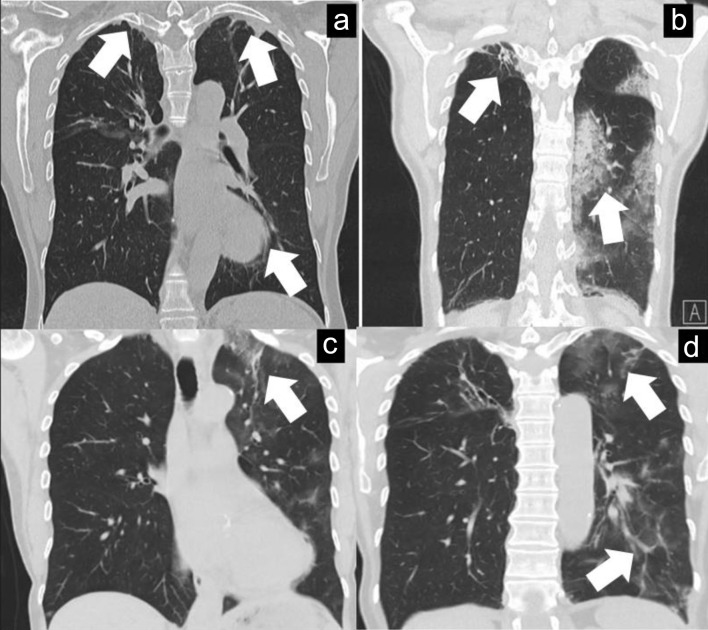

Immunocompromised patients, especially those receiving B-cell depleting therapies, are at risk for developing atypical presentation with regard to severe acute respiratory syndrome coronavirus 2 (SARS-CoV-2) infection, with the potential for diagnostic delay and adverse outcomes if such delay occurs. A 66-year-old female with history of granulomatosis with polyangiitis (GPA) with previous pulmonary involvement, treated with rituximab and low-dose prednisolone, presented with prolonged fever and cough after having been treated at home for a mild SARS-CoV-2 infection in early July 2023. The patient had a prolonged course over several months with constitutional symptoms such as fever, cough and malaise. During the investigation, which encompassed a wide range of microbiological and immunological tests, the patient was initially thought to have a flare of GPA which she was treated for without appreciable improvement, then for multiple microbiological organisms without appropriate resolution of the patient's symptoms. The differential diagnosis of prolonged SARS-CoV-2 infection was reconsidered in October 2023, and then confirmed by the presence of SARS-CoV-2 viremia through polymerase chain reaction (PCR) testing of the blood. The patient received a prolonged course of antiviral therapy with complete clinical, virological and radiological resolution. Prolonged SARS-CoV-2 infection with viremia in immunocompromised individuals needs to be considered on the differential diagnosis list in such patients presenting with constitutional symptoms, with PCR testing of the blood as a simple and effective way to establish the diagnosis.

Abstract Image